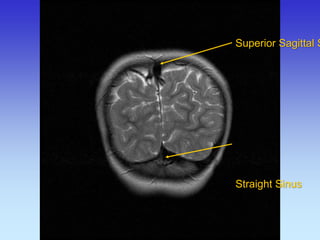

Superior Sagittal Sinus

Straight Sinus

Transverse Sinus

Superior Sagittal Straight Sinus

Cerebellum